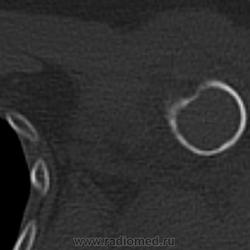

или гигантоклеточная опухоль. Требуется морфологическая верификация

Интересно, что структура разная, кость не вздута, кортикал истончен, но сохранен. Болей до травмы совершенно не было. Думаю, травматологи прооперируют, надеюсь узнать результаты гистологии - сообщу. Спасибо. Татьяна Валентиновна. Я сначала на аневризмальную кисту подумала, но не уверена была.

При ГКО бывает вторичная аневризмальная киста